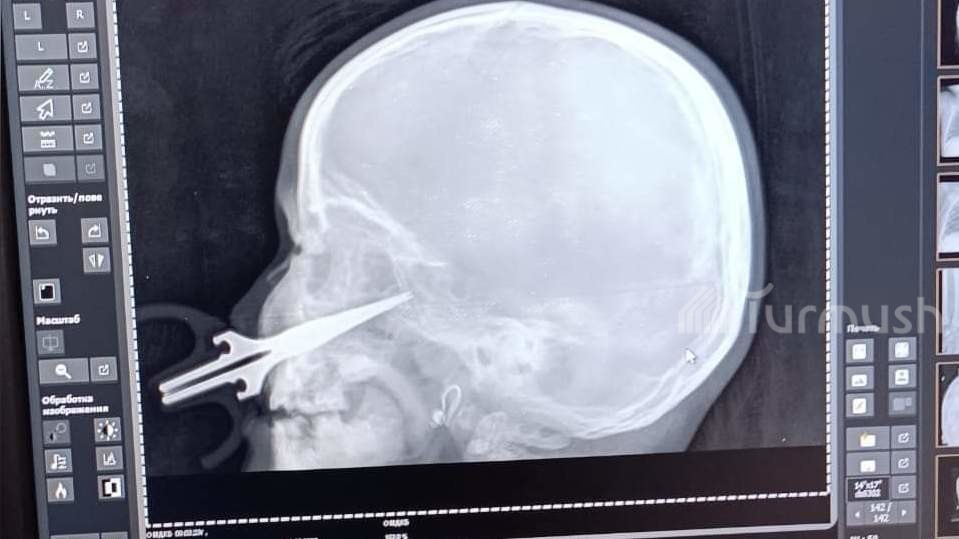

Ошто 5 жаштагы кыздын бетине кайчы сайылып калган. Сүрөт